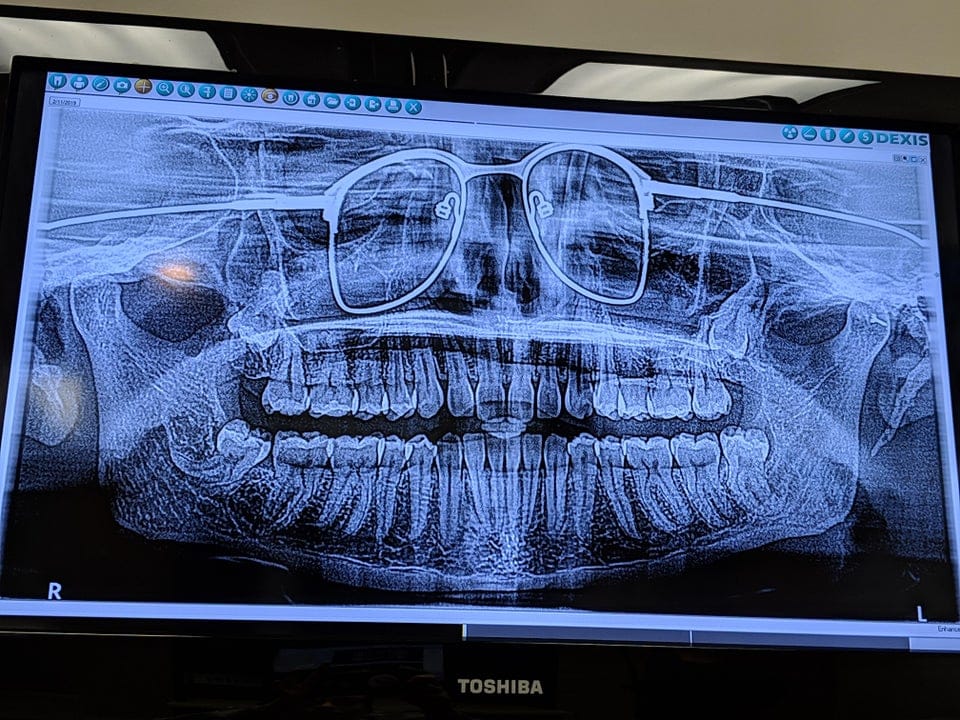

14. Стоматолог забыл попросить меня снять очки на рентгене

maggiemoocorgipoo